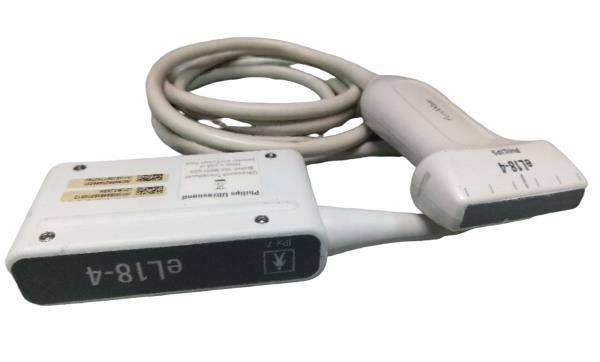

Digital Laptop External 3D Ultrasound Scanner+ Convex & Linear Probe 10" LCD CE 190891750662

Probe frequency: 2.5~10.0 MHz

probe connector: 1